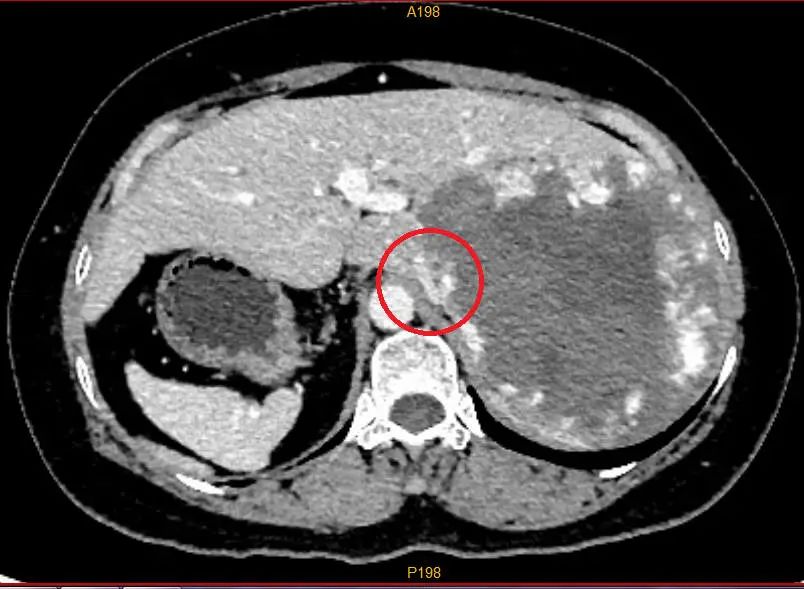

▲CT拍片可见卢女士腹腔脏器完全反位,胃及脾在右边,反位的右肝在左边,红圈处标记的下腔静脉已被巨大血管瘤压迫包绕,粘连浸润明显。图片来源:广西医科大学附属武鸣医院

据医生介绍,卢女士的血管瘤体积巨大,已经占据她整个右肝范围,必须进行手术。但是,血管瘤一旦在术中破裂,止血异常困难,手术可能危及生命。此外,卢女士反着长的器官极大增加了手术难度,属于国内外均罕见记载的疑难手术病例,手术困难重重,风险很大。